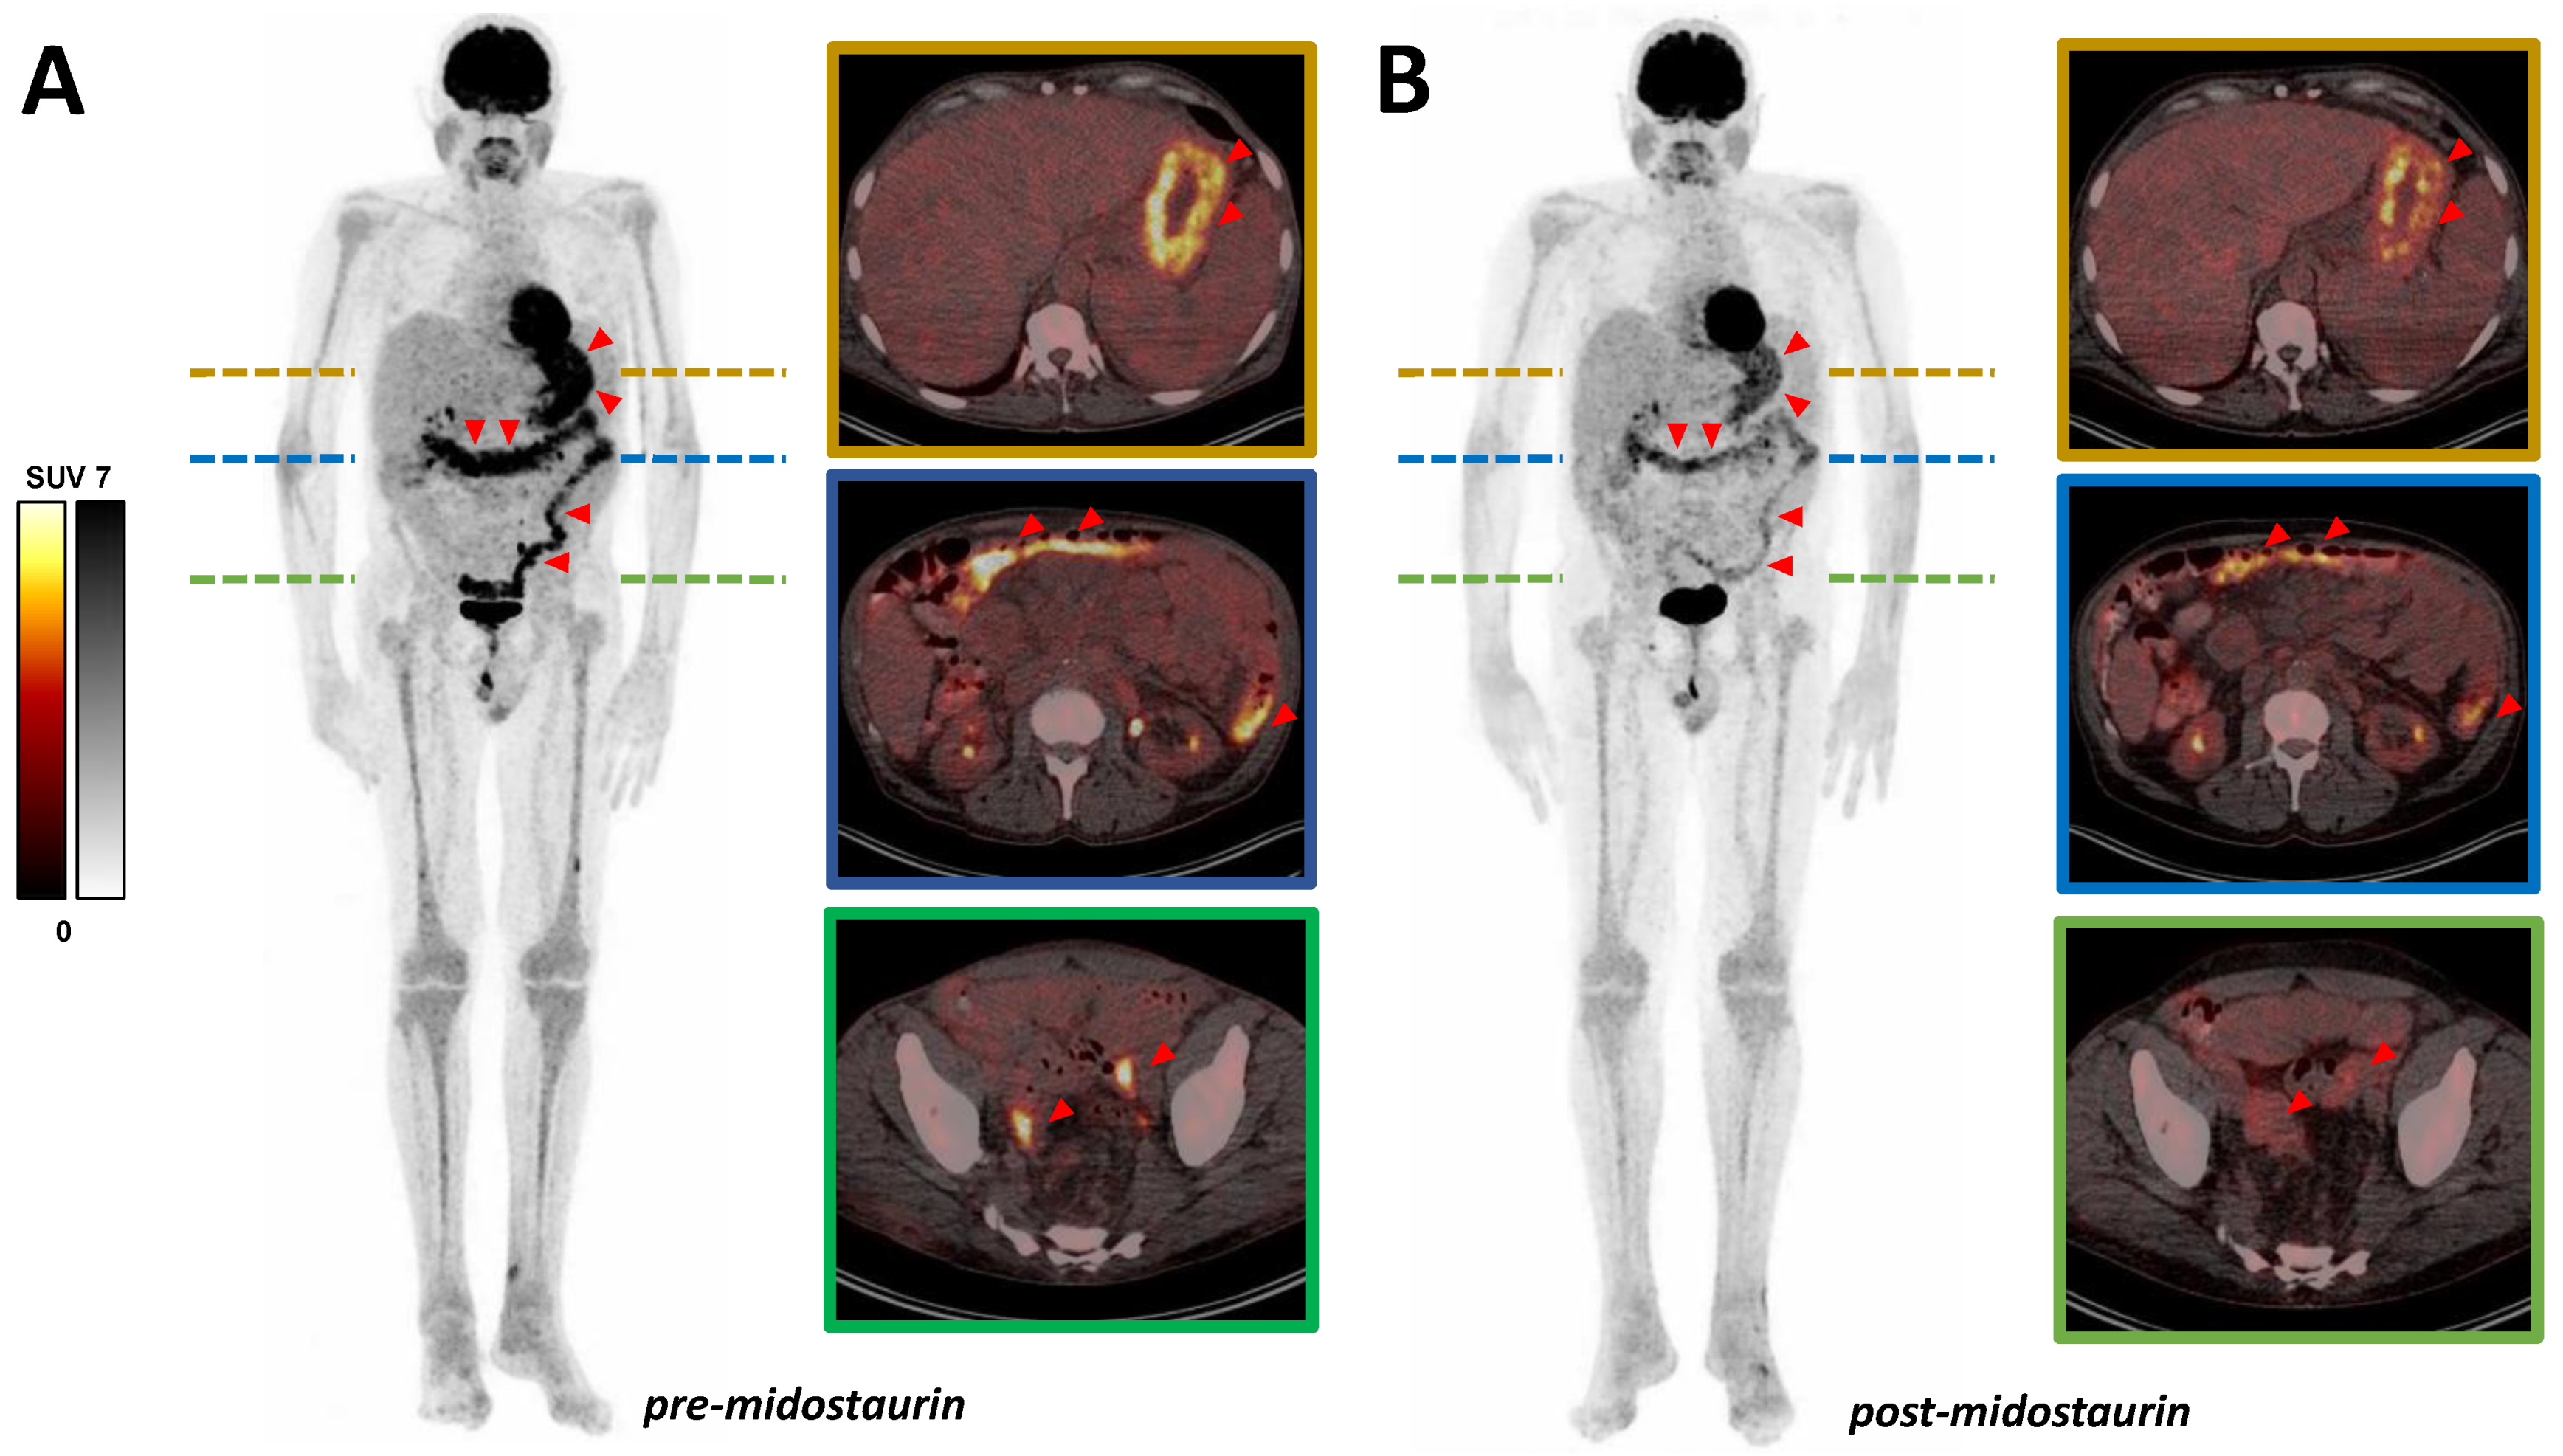

Systemic Mastocytosis Treatment with Midostaurin: [18F]FDG PET/CT as a Potential Monitoring Tool for Therapy Outcome